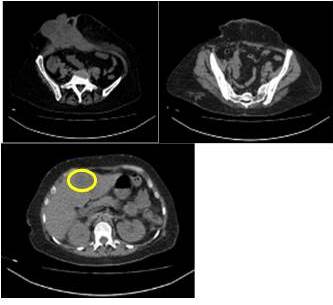

En vista de estos hallazgos, se solicitan estudios de imágenes (TAC de abdomen y pelvis 20/04/20) (Figura 3) se plantea conducta quirúrgica resección amplia más reconstrucción con malla de polipropileno a título paliativo con intención de disminución de carga tumoral.

La cirugía se realiza el 21/05/2020 teniendo cupo en la UCI y catéter de vía central, cuyos hallazgos fueron: lesión ulcerada de 20 cm x 20 cm aproximadamente que comprometía toda la pared abdominal del hemiabdomen derecho (Figura 4), epiplón con lesiones aisladas tipo nódulos los cuales fueron resecados para biopsia, no se evidenció líquido ascítico, indemnidad de asas intestinales y colon, estómago y páncreas. Se palpa lesión sólida extensa hepática segmentos II, III, IV y V, dura, muy sugerente de metástasis. Bazo aumentado de tamaño. Resto de la cavidad sin lesiones.